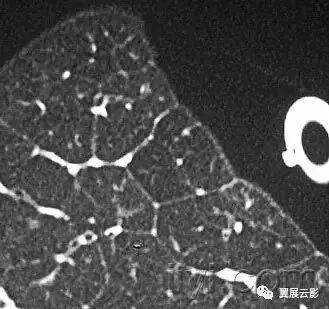

三十五、小叶

解剖:肺小叶是肺的最小结构,被小的纤维组织隔包绕。小叶也被成为次级肺小叶,包括数目不等的腺泡,呈现不规则的多边形,直径大小从1.0到2.5厘米。小叶中心结构,包括细支气管和伴行的肺小动脉、淋巴管。结缔组织分隔包绕肺小叶,内容静脉和淋巴管,与上叶、中叶的前部、外侧部、邻近纵膈处的周边部发育的较好。

CT:在薄层CT上,肺小叶的三个基本组成成分:小叶间分隔及分隔内结构,小叶中心结构,小叶实质都可以观察到,尤其是在病理状态下。与肺中心部的肺小叶相比,周边部的肺小叶表现趋于一致,形状上更加接近锥形。